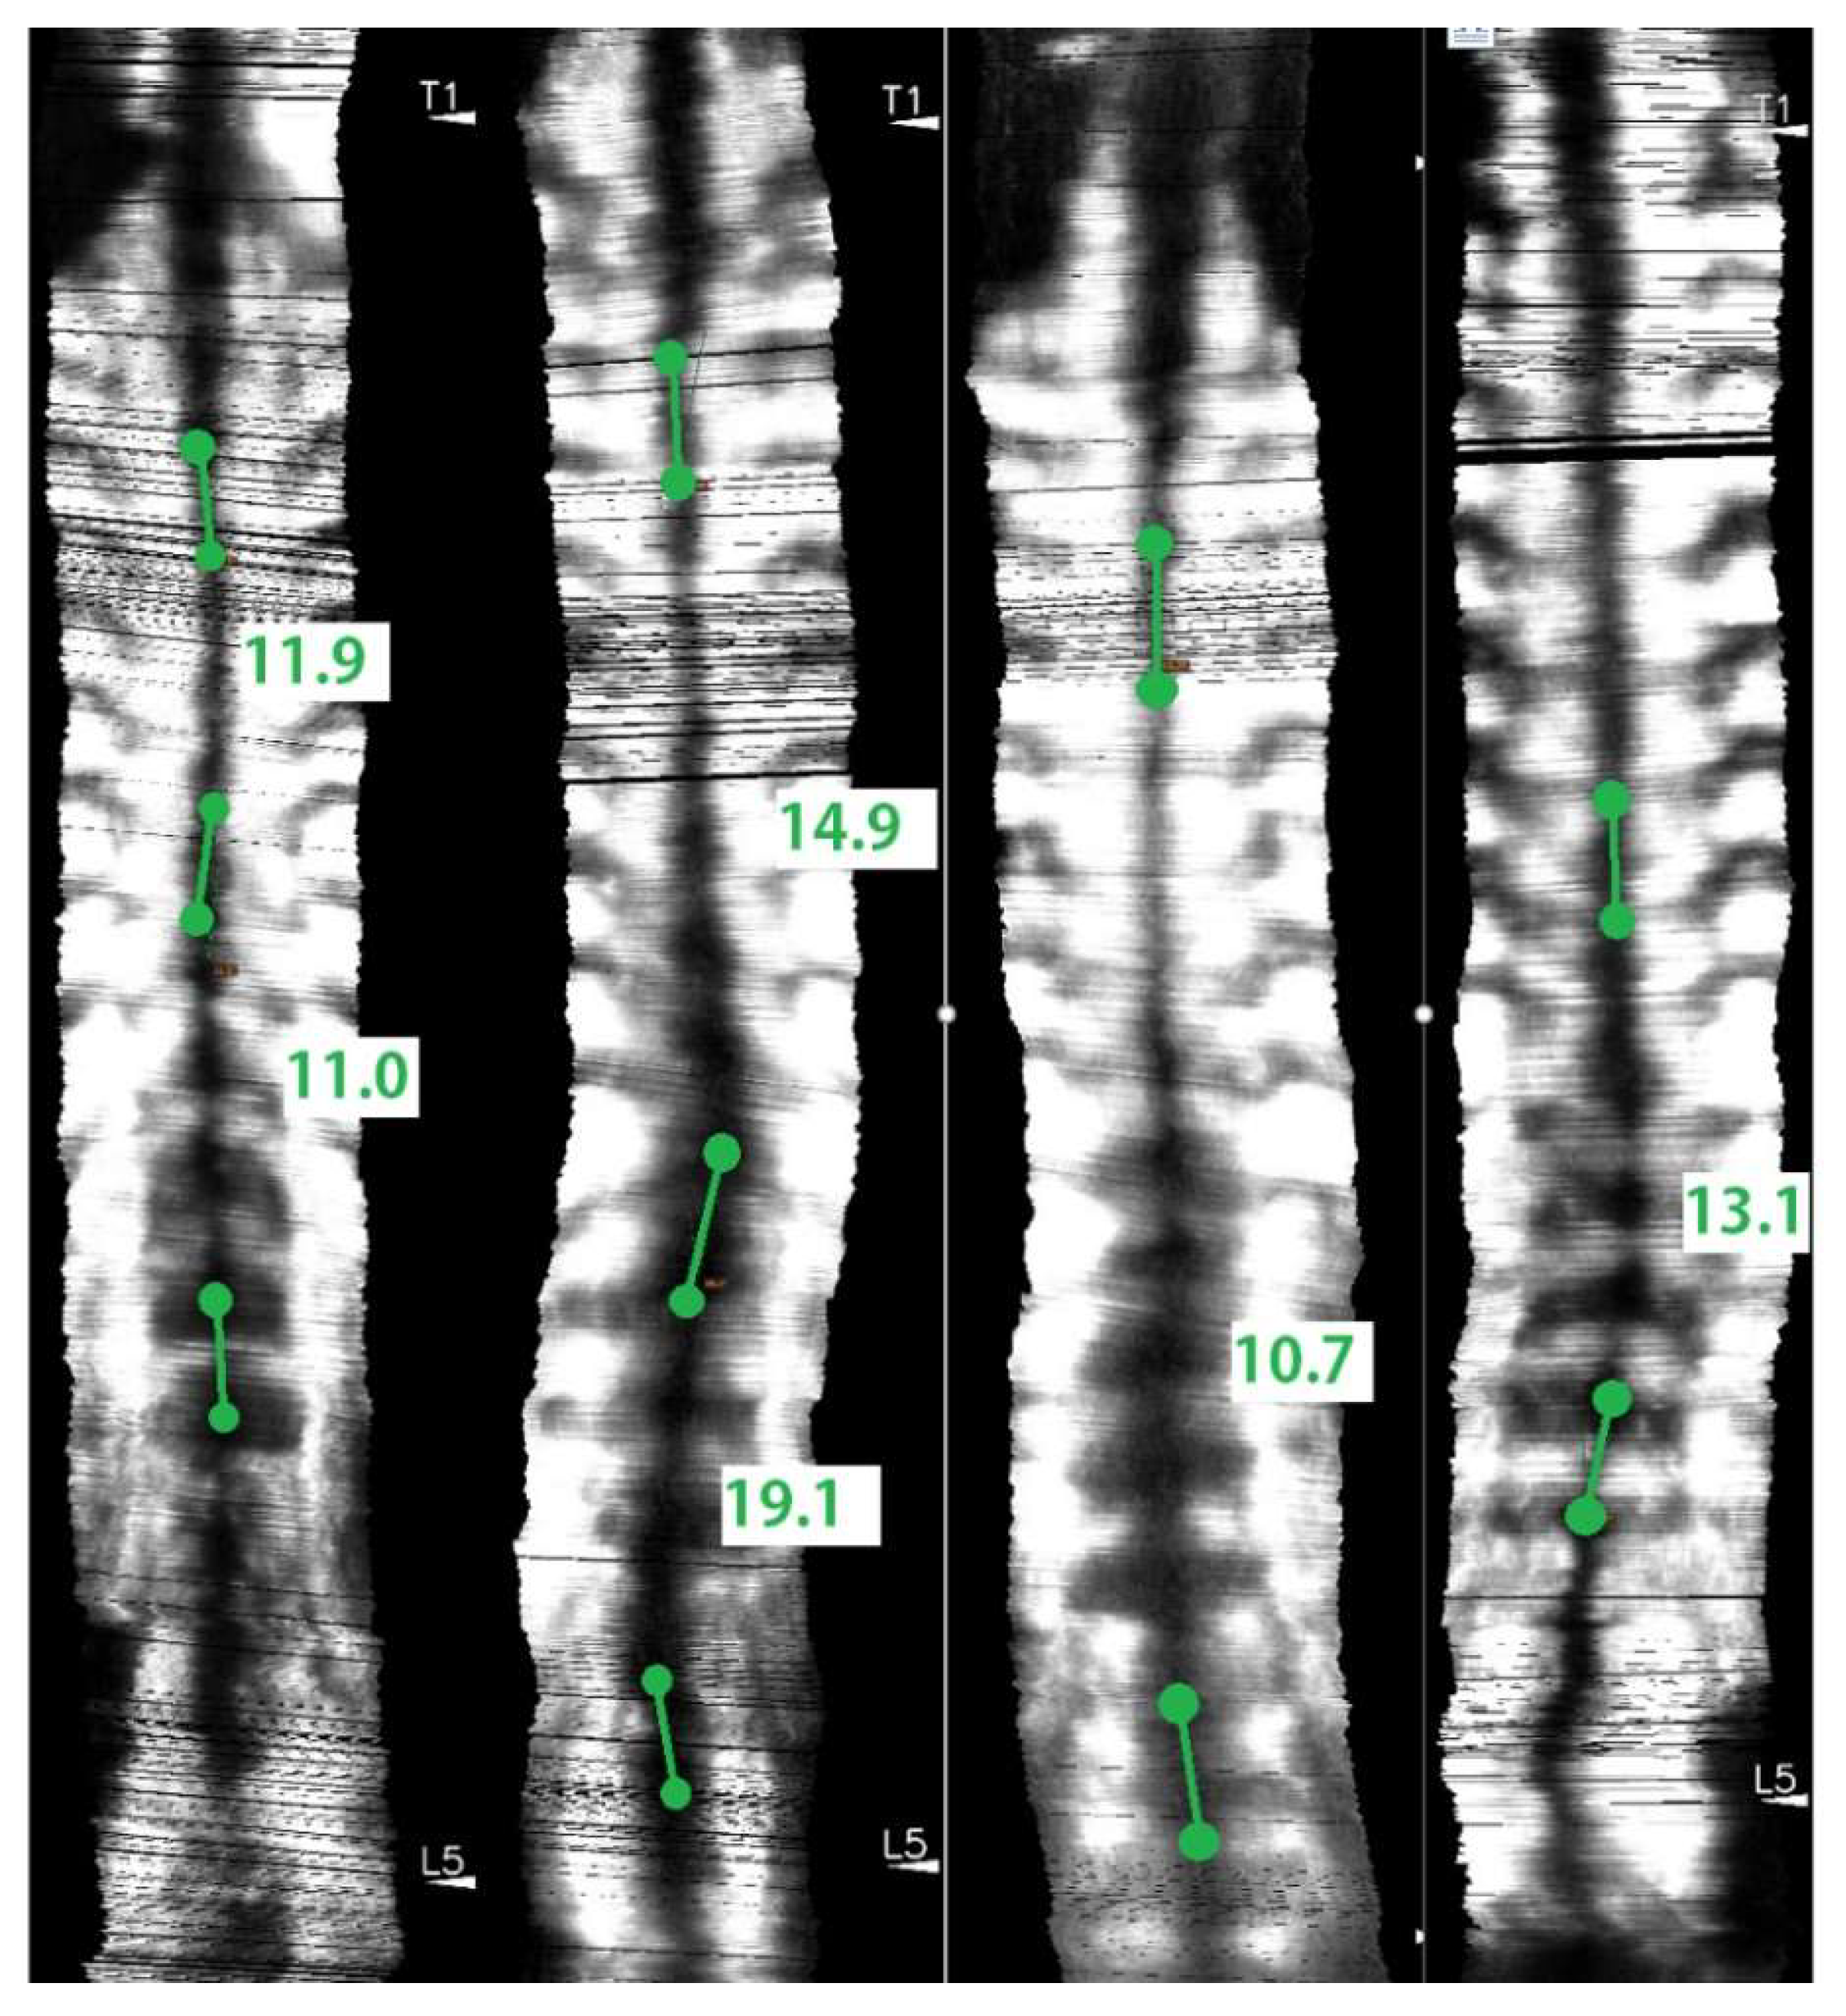

2.7. Angle Measurements and Study Design